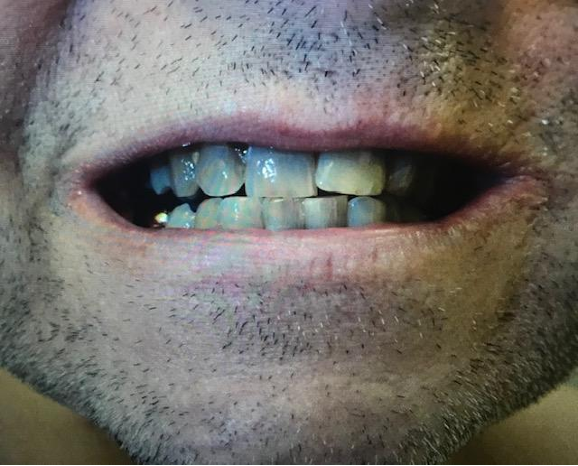

The patient agreed to be evaluated by the staff dermatologist during subsequent follow-up, who described bluish, well-demarcated patches on the sclera bilaterally. They noted a bluish dermal hue on the cartilage of the ears bilaterally. Brown-to-bluish irregular asymmetric patches on lower legs were also present with a bluish dermal hue on the fingernails. He also agreed to evaluation at the dental clinic, which found gray-blue anterior teeth and a gray-blue tinge on maxillary anterior alveolar mucosa.